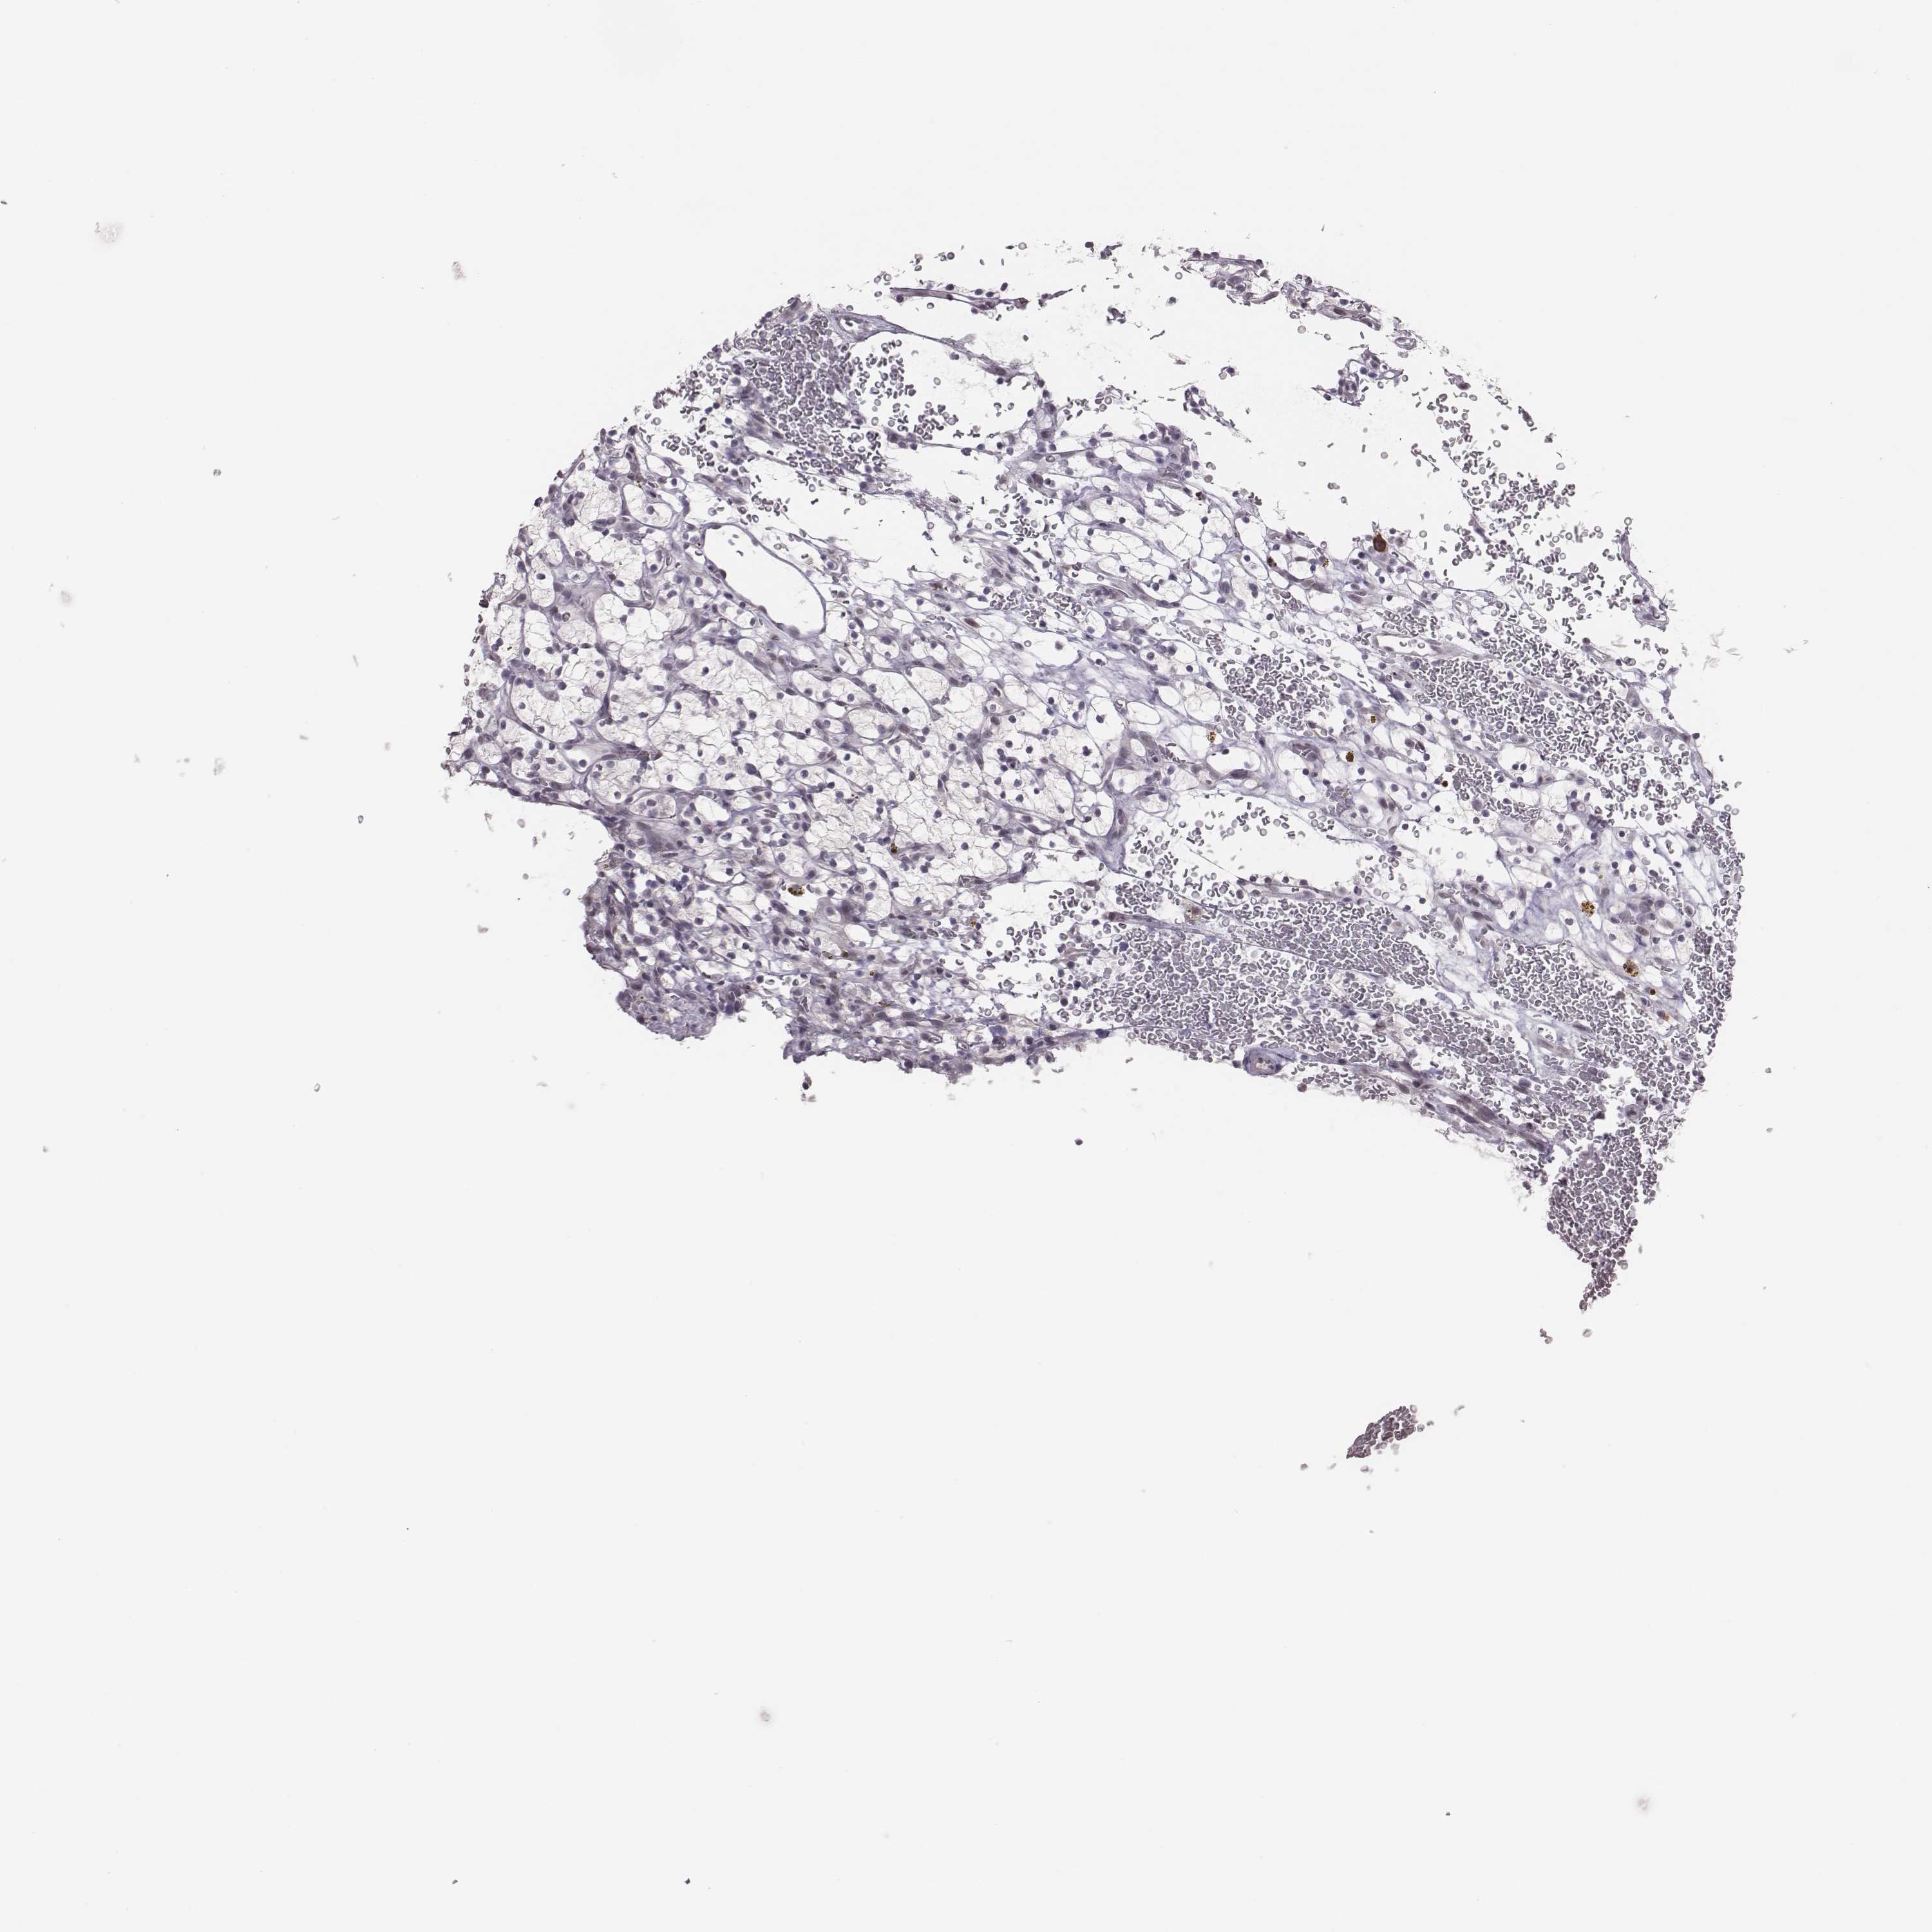

KIDNEY RENAL CLEAR CELL CARCINOMA (VALIDATION) - Interactive survival scatter ploti

The Survival Scatter plot shows the clinical status (i.e. dead or alive) for all individuals in the patient cohort, based on the same data that underlies the corresponding Kaplan-Meier plots. Patients that are alive at last time for follow-up are shown in blue and patients who have died during the study are shown in red.

The x-axis shows the expression levels (FPKM) of the investigated gene in the tumor tissue at the time of diagnosis. The y-axis shows the follow-up time after diagnosis (years). Both axes are complimented with kernel density curves demonstrating the data density over the axes. The top density plot shows the expression levels (FPKM) distribution among dead (red) and alive patients (blue). The right density plot shows the data density of the survived years of dead patients with high and low expression levels respectively, stratified using the cutoff indicated by the vertical dashed line through the Survival Scatter plot. This cutoff is automatically defined based on the FPKM cutoff that minimizes the p-score. The cutoff can be changed by dragging the vertical line or by entering a cutoff value in the square labeled "Current cut-off".

Under the Survival Scatter plot the p-score landscape (black curve; left axis) is shown together with dead median separation (red curve; right axis). Dead median separation is the difference in median mRNA expression between patients who have died with high and low expression, respectively. It is calculated as follows: median FPKM expression of dead patients with high expression - median FPKM expression of dead patients with low expression. This is intended to aid the user in visually exploring custom cutoffs and the associated p-scores and dead median separation.

Individual patient data is displayed and can be filtered by clicking on one or more of the category buttons on the top of the page. Categories describing expression level and patient information include: high, low, alive, dead, female, male and tumor stages. The scale of the x-axis can be toggled between linear and log-scale by clicking on the "x log" button. Mouse-over function shows TCGA ID, patient information and mRNA expression (FPKM) for each patient.

& Survival analysisi

Kaplan-Meier plots summarize results from analysis of correlation between mRNA expression level and patient survival. Patients were divided based on level of expression into one of the two groups "low" (under cut off) or "high" (over cut off). X-axis shows time for survival (years) and y-axis shows the probability of survival, where 1.0 corresponds to 100 percent.

PBK is potential prognostic, high expression is unfavorable in Kidney Renal Clear Cell Carcinoma (validation)

Best expression cut offi

: 3.22

TCGA RNA samplesi

RNA-seq data is reported as average FPKM (number Fragments Per Kilobase of exon per Million reads), generated by the The Cancer Genome Atlas (TCGA) .

Normal distribution across the dataset is visualized with box plots, shown as median and 25th and 75th percentiles. Points are displayed as outliers if they are above or below 1.5 times the interquartile range. FPKM values of the individual samples are presented next to the box plot.

Average pTPM 3.2

Number of samples 100